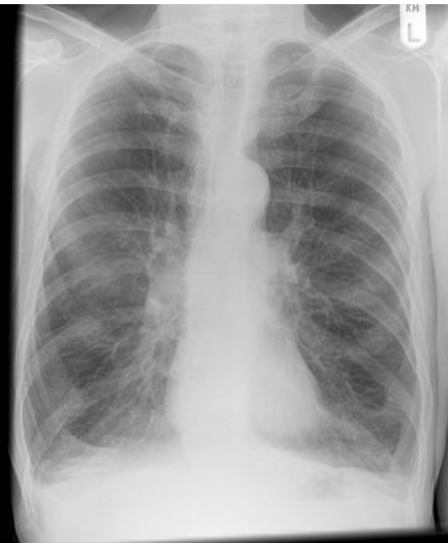

whats the dx?

COPD